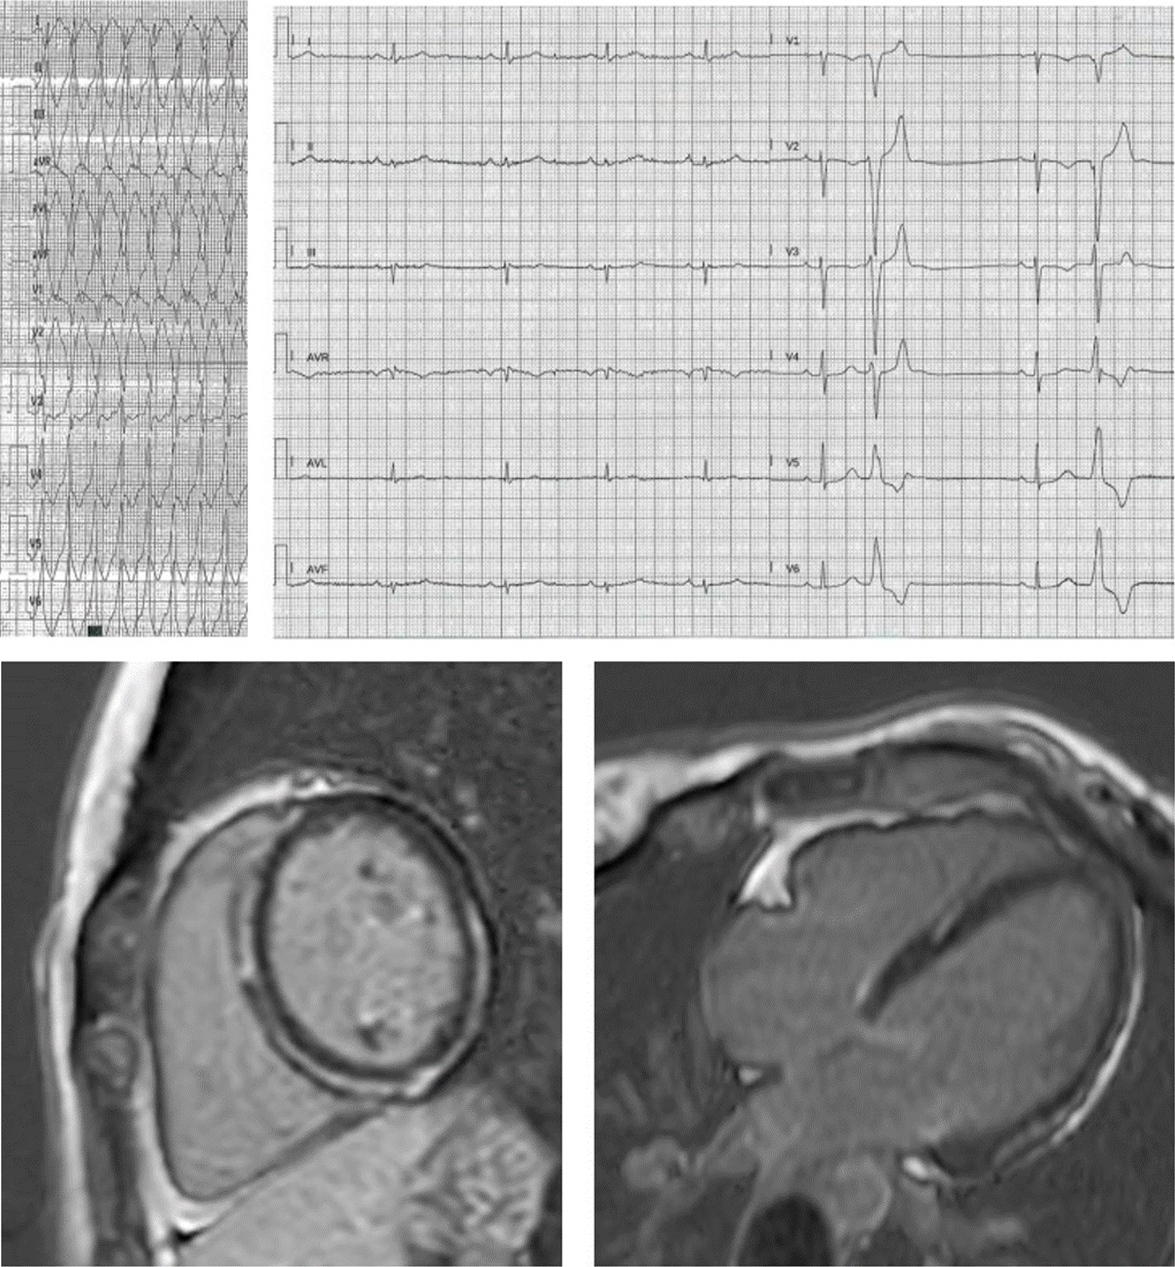

Fig. 2.Proband, aged 27 years, desmoplakin mutation: poorly tolerated monomorphic VT during training. See a midlayer ring-like fibrotic tissue involvement of the LV, without RV involvement. ECG shows low-amplitude limb leads with multifocal ventricular beats stemming from the anterior LV wall.

Fig. 3.Progressive fibrofatty replacement of the RV and later of the LV in a patient with PKP2 mutation, detected by serial ECG recordings (A) from age 44 up to 72, implanted in secondary prevention at 66 because of monomorphic VT at 210 bpm. Both ECG and CMR (B) show epicardial, midventricular and also transmural fibrotic involvement of the inferior and the posterior lateral LV wall, mimicking ischemic cardiomyopathy in the absence of coronary artery disease. The RV involvement and the progressive ECG changes along years (transition from a normal pattern to an RV and eventually to extensive LV involvement) hinted at genetic testing for the etiologic diagnosis.

Fig. 4.48 years old male, endurance sportsman, with active sarcoidosis admitted in class 4 heart failure with recurrent slow monomorphic VTs. The ECG at admission mimics ARVC with a caricatural delayed high-amplitude epsilon wave and precordial T-wave inversion resulting in QT prolongation. Clinical improvement and partial ECG modification occurred after 30 days of steroid treatment. CMR showed biventricular enlargement and systolic dysfunction, with biventricular epicardial and midventricular LGE distribution. This case highlights the diagnostic challenges in ACM.